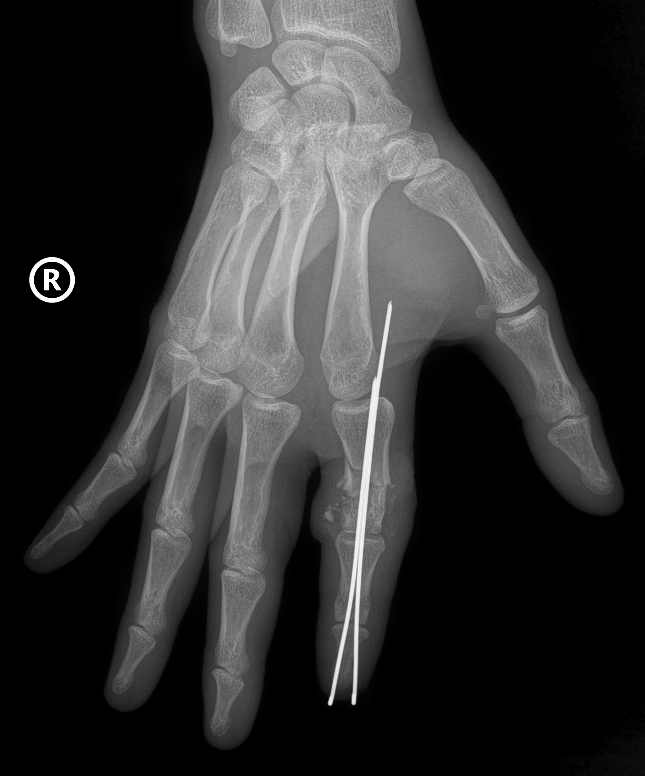

Hình ảnh phần ngón tay bị đứt rời của bệnh nhân được định vị và cố định bằng kim chuyên dụng - Ảnh: VGP

Xương ngón được định vị và cố định bằng kim chuyên dụng để tạo trục vững, hệ thống gân và dây chằng được phục hồi. Đặc biệt là thần kinh và các mạch máu nhỏ li ti chỉ khoảng 0,8 - 1mm được phục hồi với độ chính xác cao dưới kính hiển vi phẫu thuật cùng dụng cụ đặc biệt, nhằm đảm bảo phục hồi lưu thông tưới máu cho phần đứt rời.

Hiện, bệnh nhân đang được tập phục hồi chức năng để lấy lại khả năng vận động của ngón tay.Ảnh: VGP